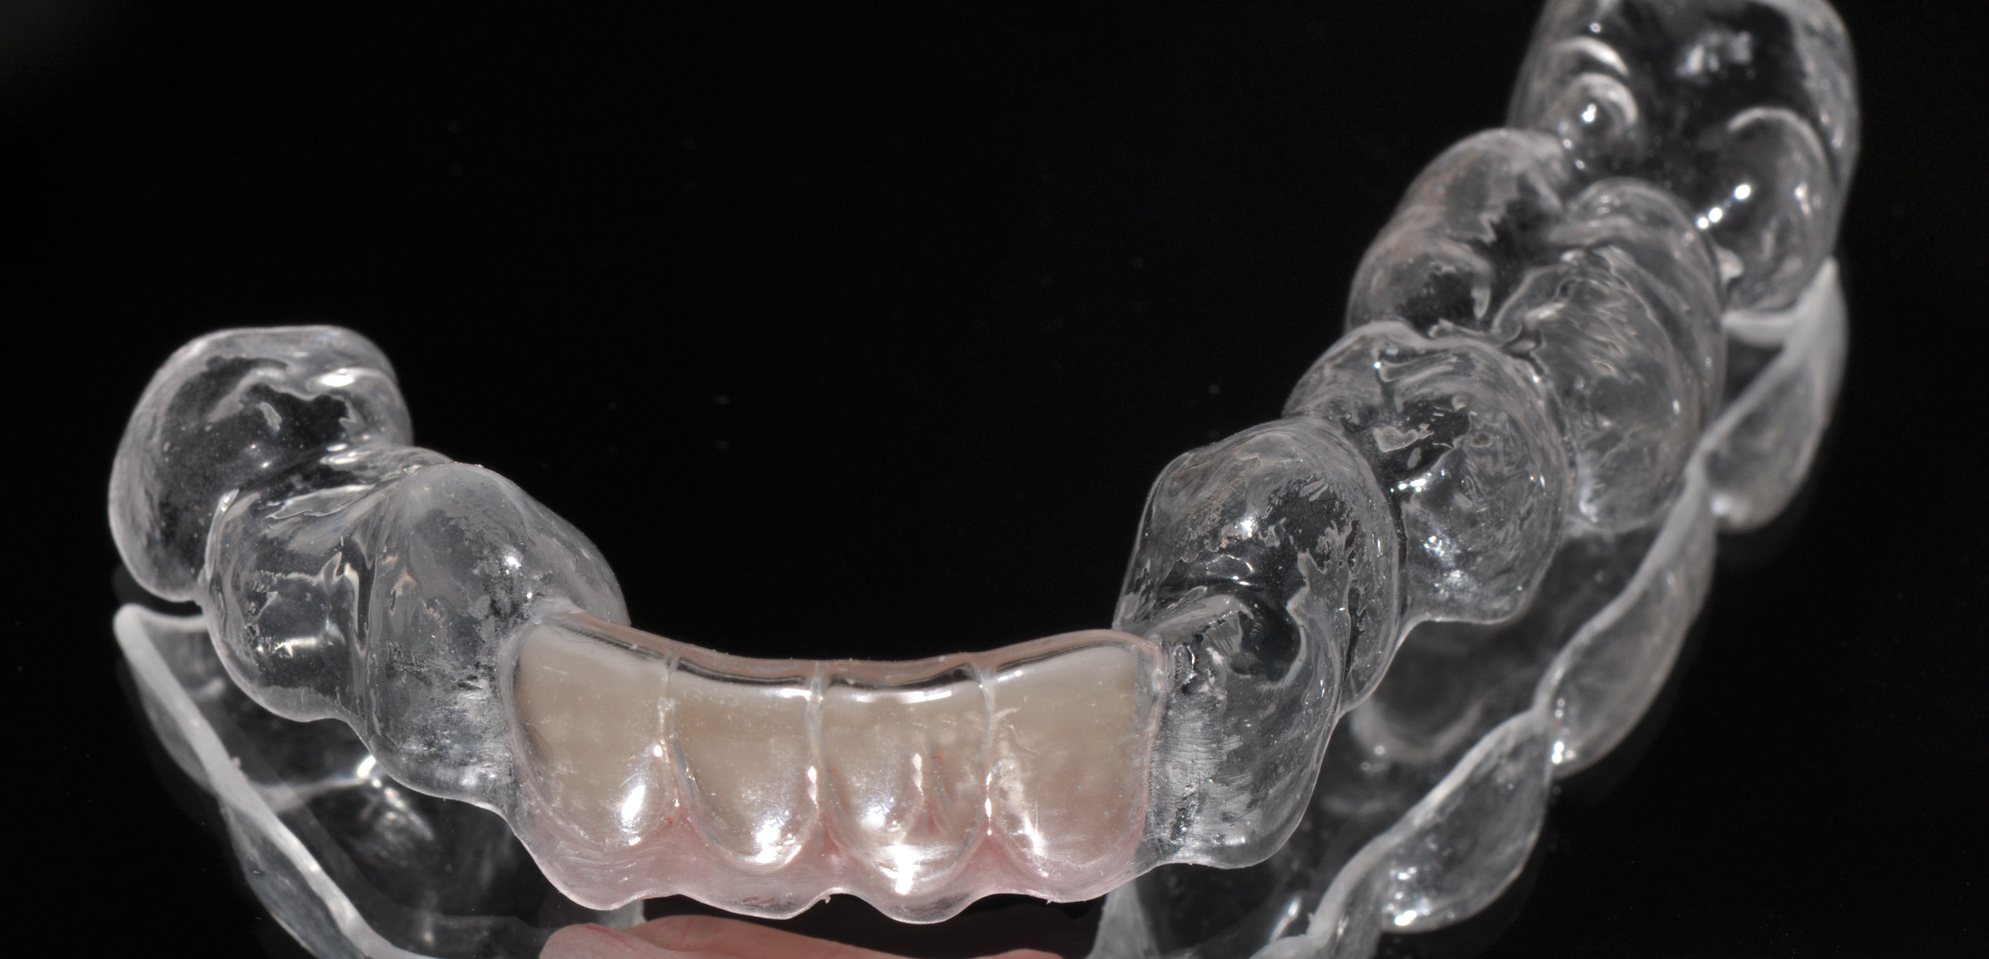

(1. AND 2.) Removable appliance.

Figure 1

Figure 2